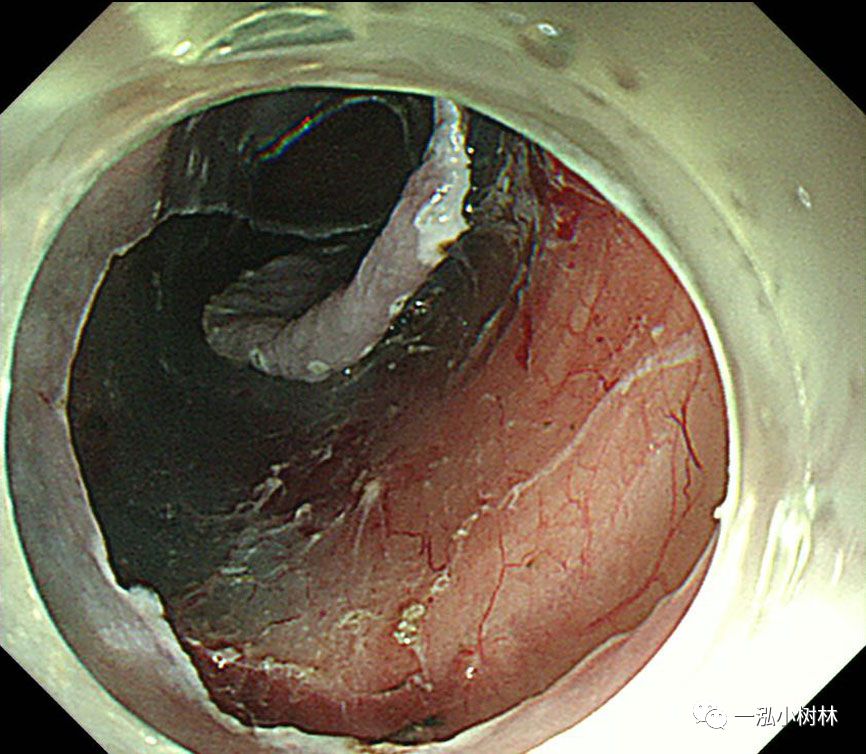

图7 使用IT刀进行纵向黏膜切口,并完成C形切口。

图8 行左侧黏膜下剥离术。在重力的作用下,黏膜剥离(左侧卧位行ESD)